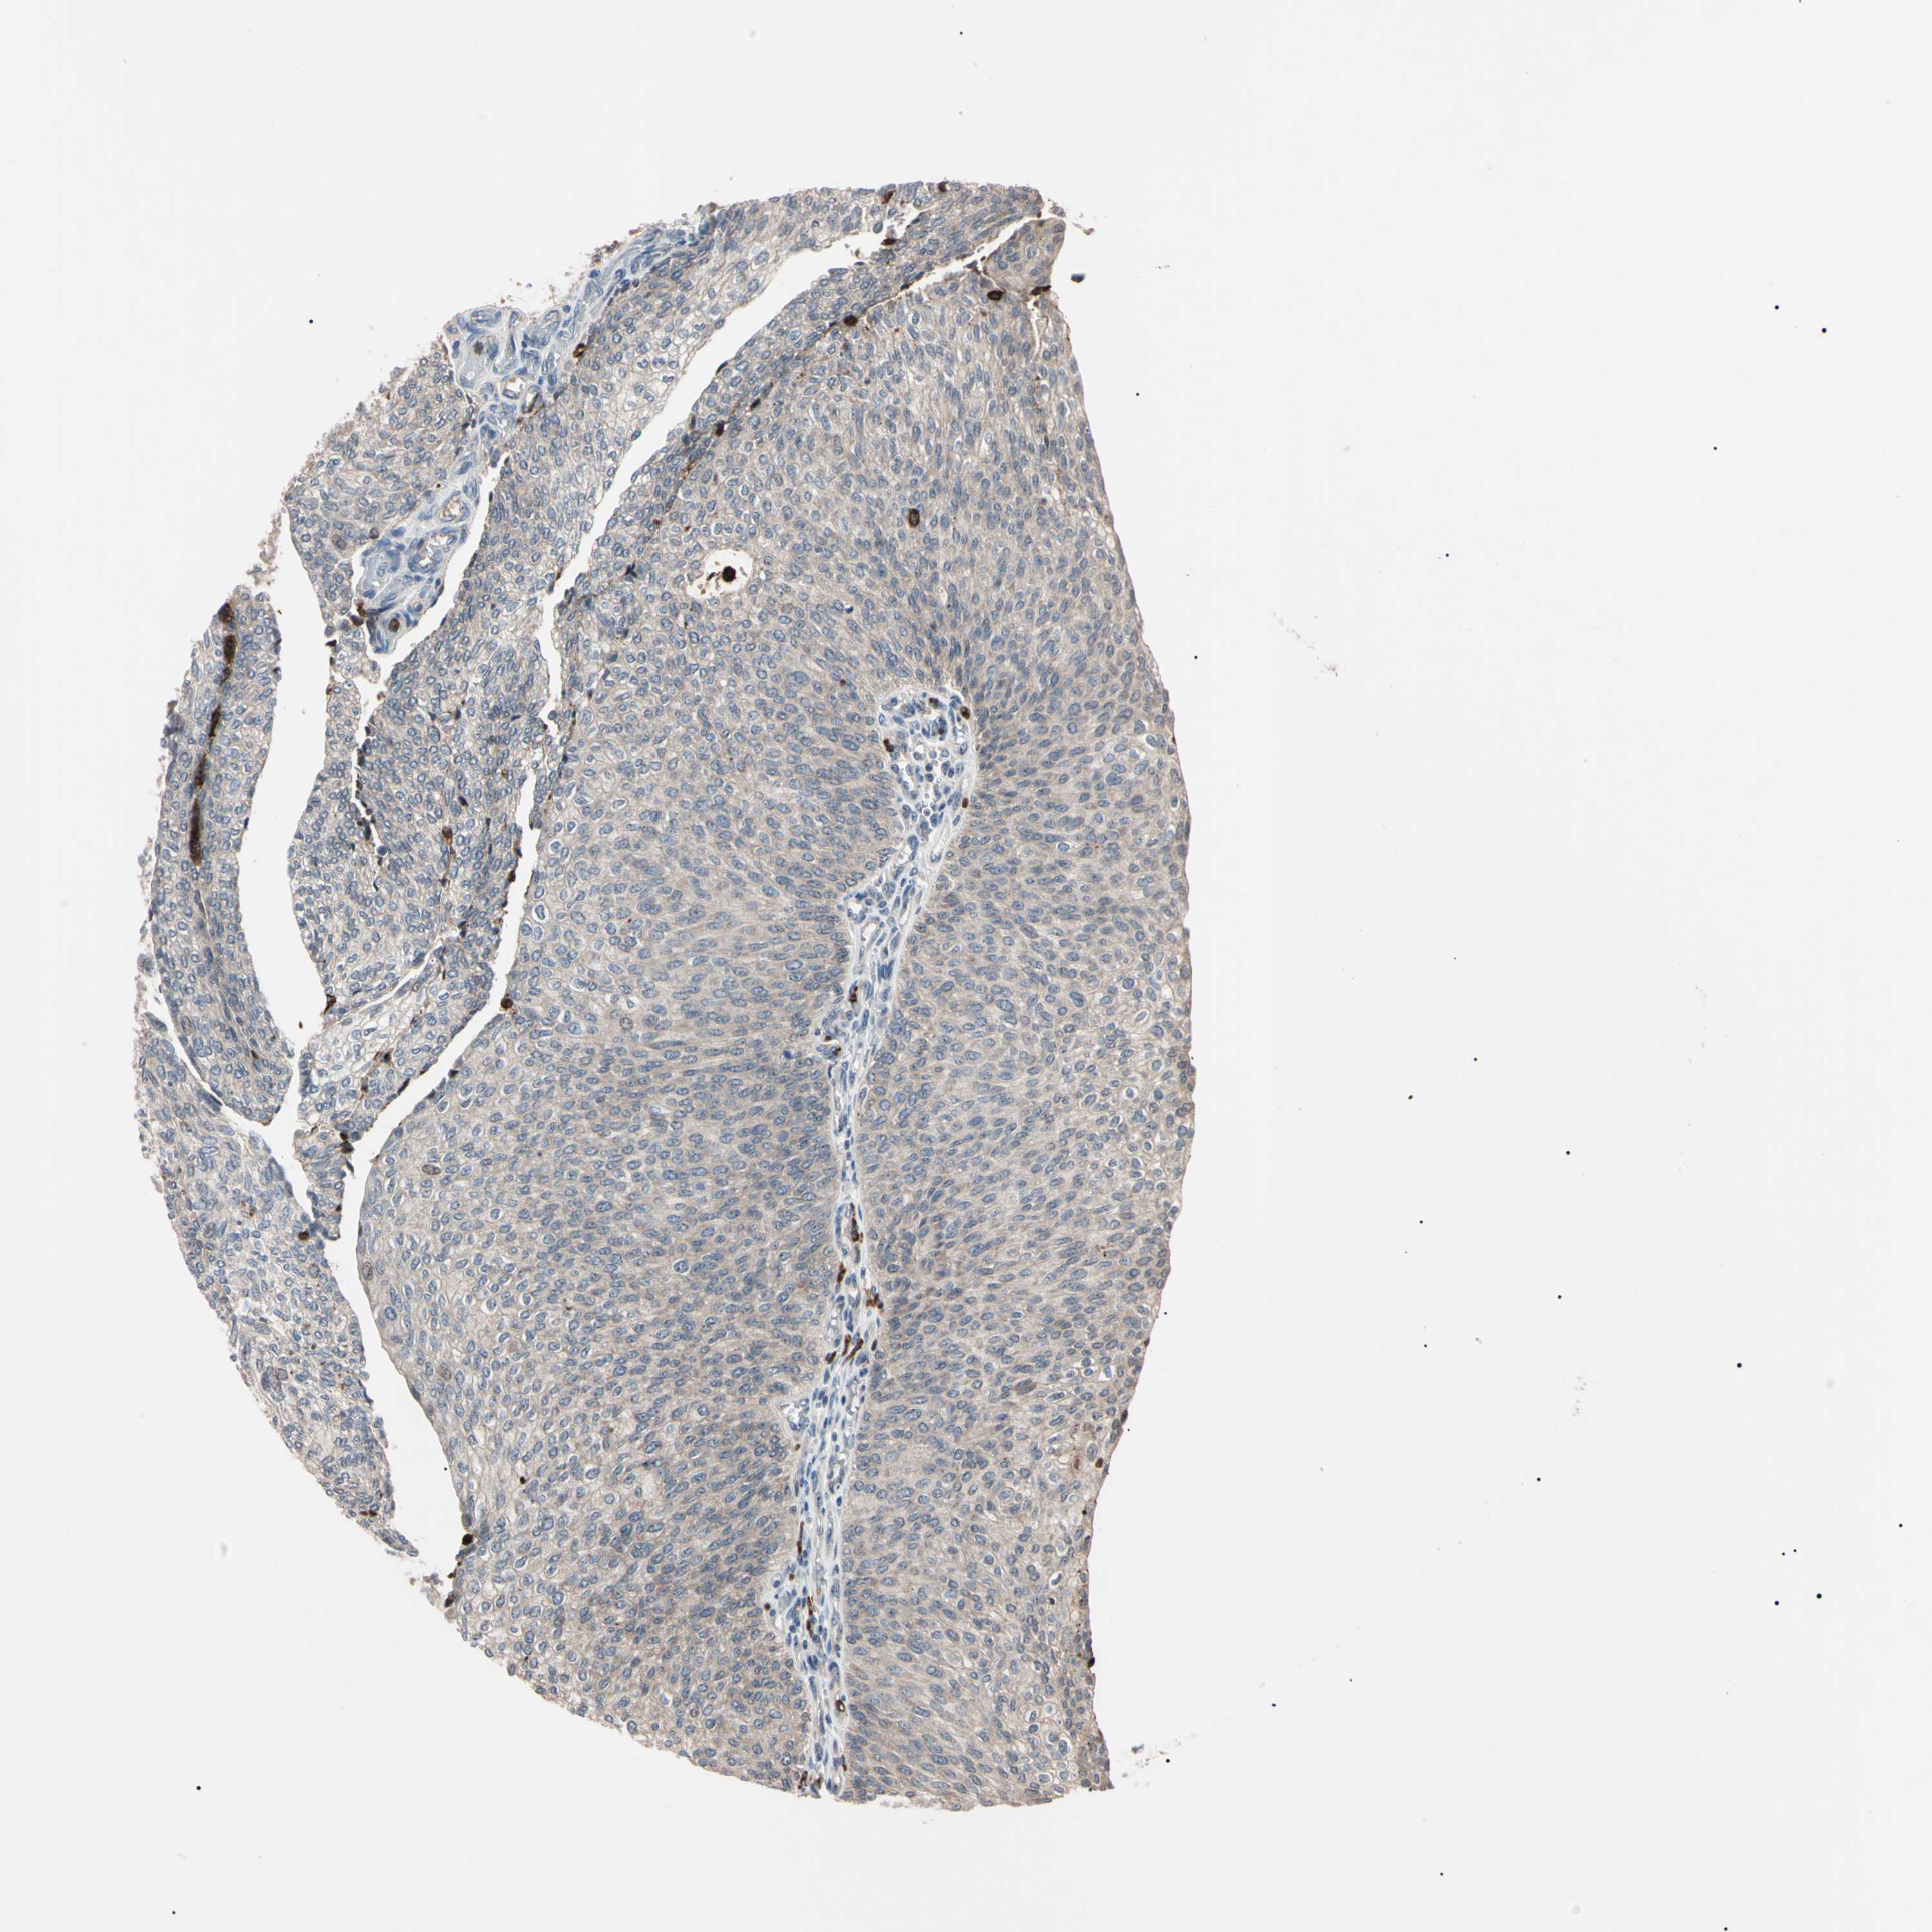

UROTHELIAL CANCER - Protein expressioni

A mouse-over function shows sample information and annotation data. Click on an image to view it in a full screen mode. Samples can be filtered based on level of antibody staining by selecting one or several of the following categories: high, medium, low and not detected. The assay and annotation is described here.

Note that samples used for immunohistochemistry by the Human Protein Atlas do not correspond to samples in the TCGA dataset.

Antibody stainingi

Antibody staining in the annotated cell types in the current human tissue is reported as not detected, low, medium, or high, based on conventional immunohistochemistry profiling in selected tissues. This score is based on the combination of the staining intensity and fraction of stained cells.

Each image is clickable and will lead to virtual microscopy that enables deeper exploration of all samples and also displays staining intensity scores, fraction scores and subcellular localization as well as patient and tissue information for each sample.

Antibody HPA008052

Antibody CAB010277

Staining

High

Medium

Low

Not detected

Intensity

Strong

Moderate

Weak

Negative

Quantity

>75%

75%-25%

<25%

None

Location

Nuclear

Cytoplasmic/membranous

Cytoplasmic/membranous,nuclear

Urothelial carcinoma, Low grade

Urothelial carcinoma, High grade